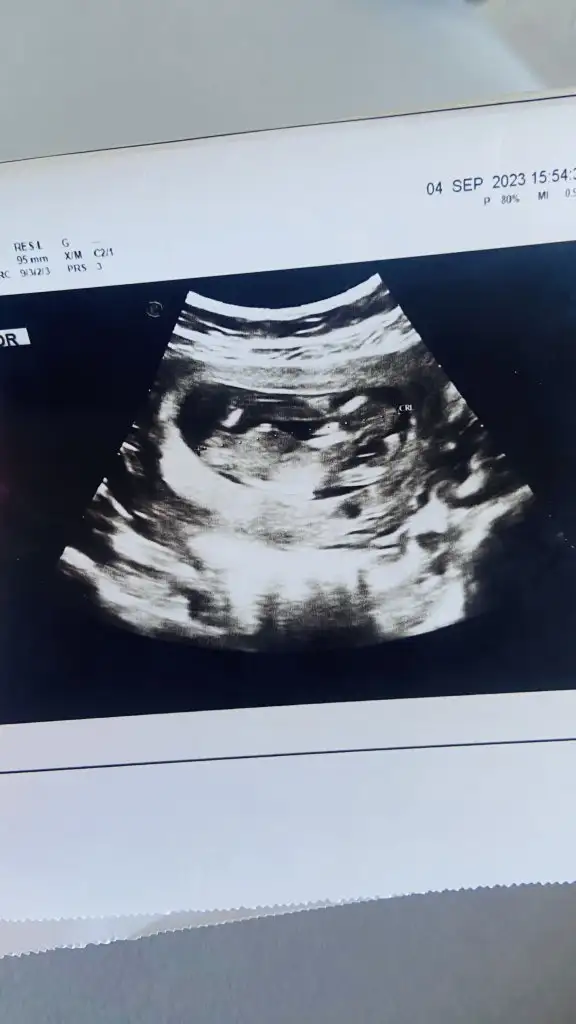

Fetal dna testi kromozom 21 anomalisi çıkmış bitmiş durumdayim

Canım insallah yanlışlık vardır Şubat annelerindeki arkadas demişti fetal DNA da anomali çıkmış amniyosentez yaptırmış temiz gelmiş hemen telaşa kapılma kaç haftaliksin 2li test geçtiyse 3 lu yaptır birde doktorunla görüştün mü detaylı ultrason da yaptır down için bir kaç şeyin bebekte olması lazım kalpte delik bağırsakta parlaklık burun kemiği olmaması ense kalınlığı gibi gibi inşallah yanlışlık vardır canım benim